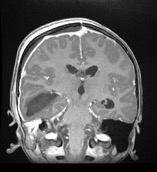

Diagnostic testing. Findings from the laboratory studies revealed an elevated white blood cell count of 33.09 c/mL, an elevated erythrocyte sedimentation rate of 122 mm/hr, and an elevated procalcitonin level of 9.61 ng/mL. Thus, the patient was started on cefepime and levetiracetam. Imaging studies demonstrated mastoiditis, a large right temporal collection of fluid concerning for early cerebritis, and ventriculitis with abscess formation and local mass effect (Figures 1-4).

Figure 3. Postcontrast coronal magnetic resonance imaging demonstrated a large right temporal collection concerning for early cerebritis with abscess, decompressing into the ventricular system with presence of ventricular abscesses. There is evidence of pachymeningitis and small right frontoparietal epidural abscess with local mass effect.